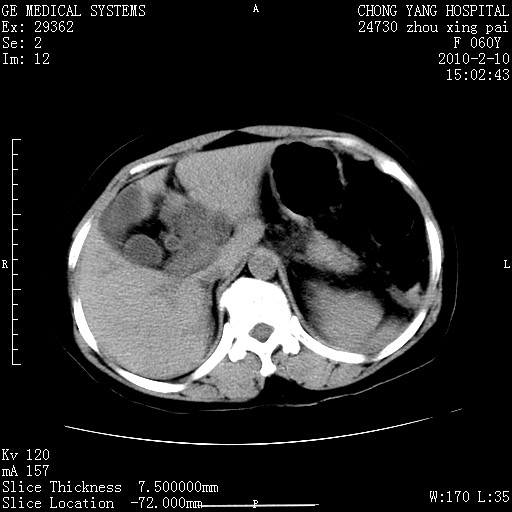

标题: CT24682:F60Y 腹痛 其它不详 [打印本页]

标题: CT24682:F60Y 腹痛 其它不详

胆总管末端梗阻!结石?肿瘤?建议增强!必要时行ercp!

胆总管末端梗阻!结石?胰腺影增粗,以胰腺头部为著,胰周看见渗出影,双侧胸腔积液,(胸膜反应)考虑胰腺炎。

1)胆总管末端梗阻,不排除结石所致可能。2)胰腺炎。3)慢性胆囊炎可能。4)左侧输尿管上段扩张。5)少量腹水。6)双侧少量胸腔积液,伴两下肺部分肺萎陷。

1)胆囊炎。2)胆源性胰腺炎。3)右肾周筋膜增厚,肾旁前间隙积液。4)左侧输尿管上段扩张。5)少量腹水。6)双侧少量胸腔积液,伴两下肺部分肺膨胀不全。

急性胰腺炎所致胆总管扩张!

1)胆总管末端梗阻。2)胰腺炎。3)慢性胆囊炎可能。4)左侧输尿管上段扩张。5)少量腹水。6)双侧少量胸腔积液,伴两下肺部分肺萎陷。